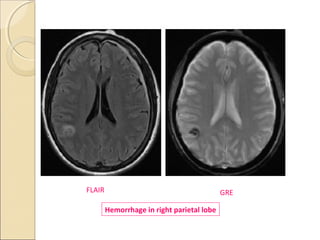

GREGRE

 In a GRE sequence, an RF pulse is applied that

partly flips the NMV into the transverse plane

(variable flip angle).

Gradients, as opposed to RF pulses, are used to

dephase (negative gradient) and rephase (positive

gradients) transverse magnetization.

Because gradients do not refocus field

inhomogeneities, GRE sequences with long TEs

are T2* weighted (because of magnetic

susceptibility) rather than T2 weighted like SE

sequences

 GRE Sequences contd:

 This feature of GRE sequences is exploited- in

detection of hemorrhage, as the iron in Hb becomes

magnetized locally (produces its own local magnetic

field) and thus dephases the spinning nuclei.

 The technique is particularly helpful for diagnosing

hemorrhagic contusions such as those in the brain .

 SE sequences, on the other hand- relatively immune

from magnetic susceptibility artifacts, and also less

sensitive in depicting hemorrhage and calcification.

GREFLAIR

Hemorrhage in right parietal lobe